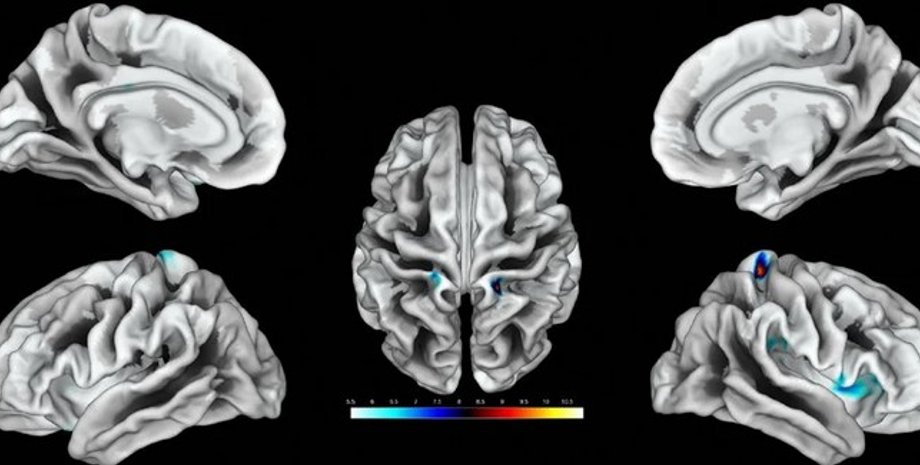

Ділянки мозку, що відповідають за клітор, виділені кольором. | Фото: ScienceAlert

Дослідники виявили ділянки мозку, які відповідають за реакцію на дотик до геніталій жінок. Виявилося, що вони розвиненіші в тих, хто займається сексом частіше.

Під час дослідження проводилася стимуляція клітора 20 дорослих жінок, під час якої сканування мозку здійснювалося за допомогою функціональної магнітно-резонансної томографії. Ученим вперше вдалося нанести на карту ділянки мозку, які відповідають за реакцію на дотик до геніталій у жінок. За словами дослідників, ці результати можна використовувати для лікування жінок, які страждають від сексуальної дисфункції, повідомляє ScienceAlert.

Стимулювання клітора відбувалося 8 разів поспіль протягом 10 секунд з 10-секундними перервами. У результаті сканування ділянок мозку вчені визначили, які саме з них відповідають за жіночі геніталії. Також учені з'ясували, що у жінок, які мають частіші сексуальні контакти, ці ділянки збільшені в розмірах.

"Ми виявили зв'язок між частотою статевого акту і товщиною окремих, нанесених на карту ділянок. Чим більше сексу, тим більша ця ділянка", — говорить Хайм.